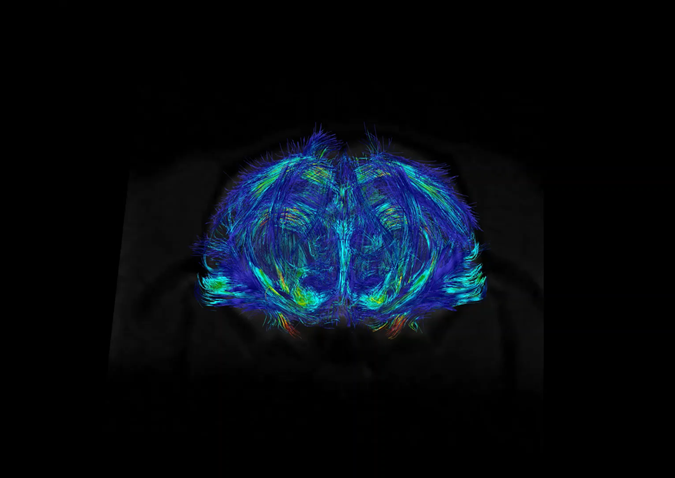

- Difüzyon tensör görüntüleme (DTI), traktografi

Difüzyon Görüntüleme Uygulamaları

Dokulardaki (örneğin beyin, karaciğer) difüzyon özellikleri difüzyon ağırlıklı görüntüleme sekansları ile değerlendirilebilmektedir. Buna ek olarak, beyindeki beyaz cevher yolaklarının fraksiyonel anizotropi (FA) gibi ayrıntılı özelliklerini değerlendirmeye ve traktografisine olanak tanıyan difüzyon tensor görüntüleme yapılabilmektedir.